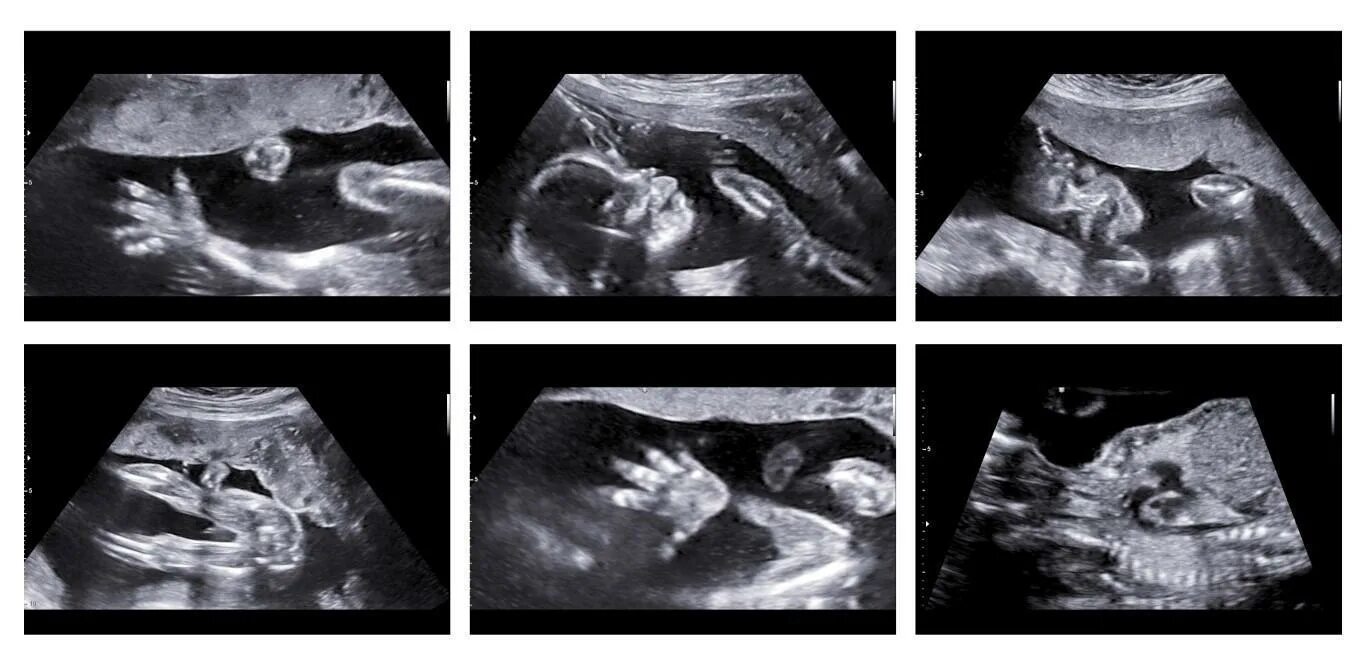

Как определить пол на 20 неделе